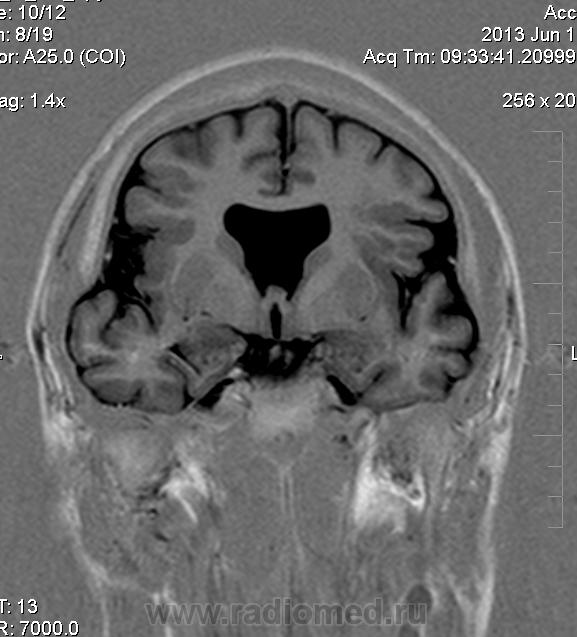

Мужчина 32 лет. Из анамнеза: перинатальное повреждение ЦНС, ДЦП, дизартрия, правосторонний верхний монопарез. С 16 лет приступы эпилепсии.

Аплазия прозрачной перегородки. Шизэнцефалия с открытыми краями в лобно-теменной области слева. Шизэнцефалия с закрытыми краями в лобной области справа? Утолщение коры по контуру расщелин и в области глазничной извилины правой лобной доли. Микрогирия? Гиперостоз костей свода черепа. Уважаемые коллеги, возможно я ошибаюсь, или есть еще аномалия?

Спасибо. Как тогда лучше сформулировать заключение? МР-картина кортикальной дисплазии : двусторнняя шизэнцефалия с утолщением коры по контуру расщелин, микрогирия в лобной области справа, очаг гетеротопии серого вещества в области  глазничной извилины правой лобной доли. Признаки септооптической дисплазии (гипоплазия зрительных нервов, аплазия прозрачной перегородки). Лиссэнцефалии не вижу. Есть сомнения по поводу шизэнцефалии справа (может быть я запуталась в микрогирии и мерещится шизэнцефалия?) Нет ли какой либо анамалии развития черепа?

На мой взгляд, полимикрогирия двусторонняя (конвекситальные отделы дорзальных отделов лобных долей и частично теменных, а также в базальном отделе полюса правой лобной доли) + закрытая шизенцефалия левой лобно-теменной области. Аплазия прозрачной перегородки (как признаки лобарной голопрозенцефалии).